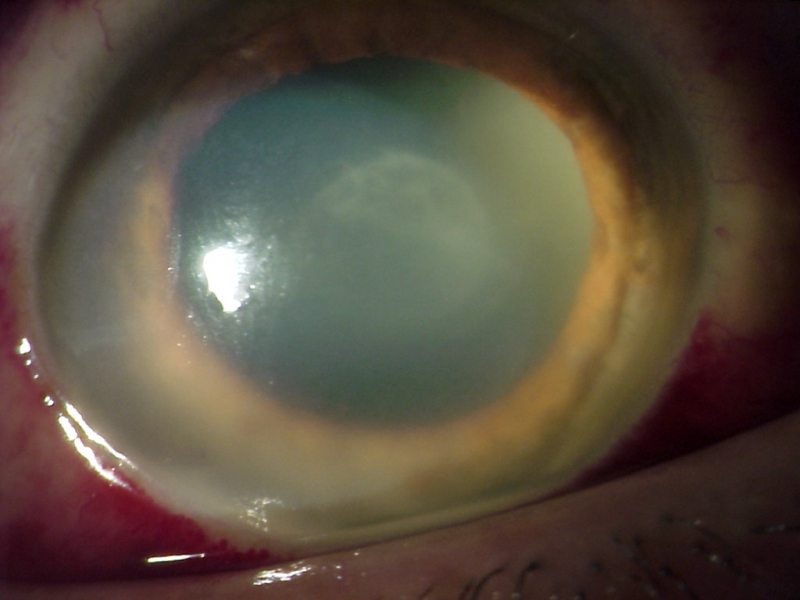

El hipopion (Figura 2) puede estar presente hasta en un 85.7% y su evolución en las primeras horas puede orientarnos sobre la severidad del cuadro. También se pueden ver mallas de fibrina en área pupilar (Figura 3), que se dirigen en ocasiones hacia la incisión y la paracentesis y ante las cuales debemos realizar el diagnóstico diferencial con las uveítis postquirúrgicas del paciente diabético. Se puede observar edema corneal epitelial y/o estromal (Figura 4), infiltrados (pudiendo provocar incluso melting corneal), defectos epiteliales, abscesos en la zona de los puntos corneales, etc..

En casos iniciales se puede observar células blanquecinas en vítreo anterior, que suele evolucionar rápidamente hacia vitritis densa que nos hará difícil valorar detalles retinianos o frecuentemente no se ve ningún detalle simplemente un reflejo amarillento-blanquecino, signo de gravedad severa (Figura 5). En casos en los que la vitritis no es muy severa es posible observar hemorragias intraretinianas en semiperiferia así como periflebitis, hallazgos que en la fase más precoz puede ayudar a orientar el cuadro de endoftalmitis infecciosa12.

Figura 2. Hipopion.

Figura 3. Malla de fibrina en el área pupilar.

Figura 4. Edema corneal asociado a endoftalmitis.

Figura 5. Vitritis densa.